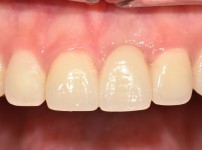

Smilefit 심미보철

심미보철